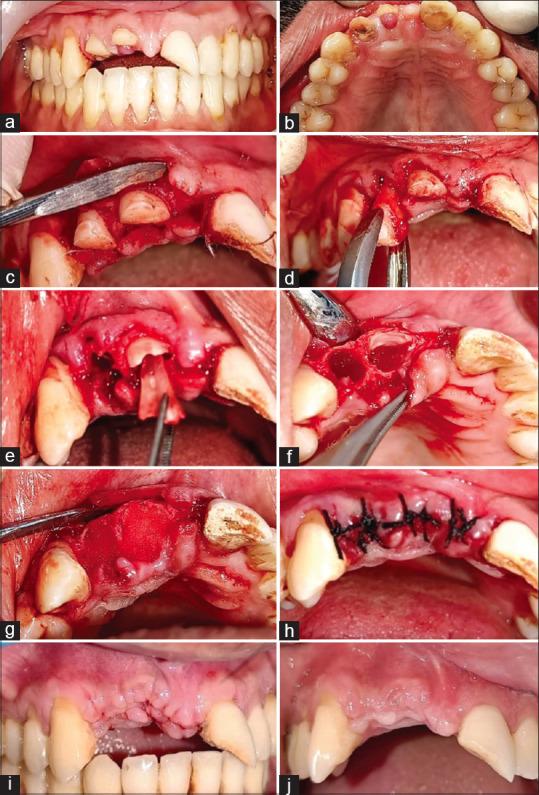

MATERIALS AND METHODS

Twenty-six sites, i.e., 13 sites requiring partial tooth extraction (test sites) and 13 sites with whole tooth extraction (control sites), in the maxillary anterior region were included. In each patient, at least two sites were included (one test and one control). After both procedures, a collagen sponge was placed in the socket and sutured with silk suture. The height of the labial crestal bone and width of the socket at both sites were evaluated by the cone-beam computed tomography examination preoperatively at baseline and after a 3-month follow-up period.

纳入上颌前部区域的26个位点,即13个需要部分拔牙的位点(试验位点)和13个全牙拔除的位点(对照位点)。每位患者至少纳入两个位点(一个试验位点和一个对照位点)。两种操作后,在牙槽窝内放置胶原海绵并用丝线缝合。通过锥形束计算机断层扫描检查在术前基线以及3个月随访期后评估两个位点的唇侧牙槽嵴骨高度和牙槽窝宽度。